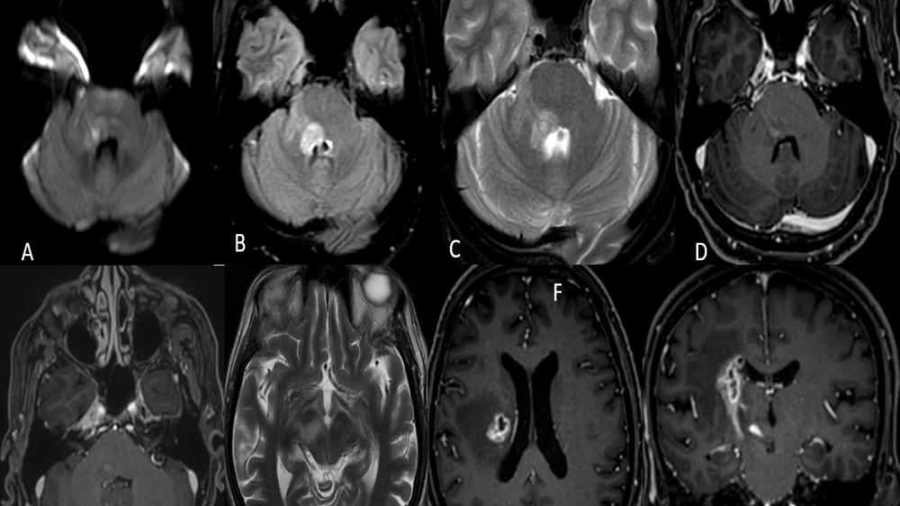

11 year old female child presented with history of right sided hearing loss, vertigo and imbalance since 6 months, right facial numbness, facial asymmetry and difficulty swallowing since 3 months, headache and vomiting since 1 month duration.